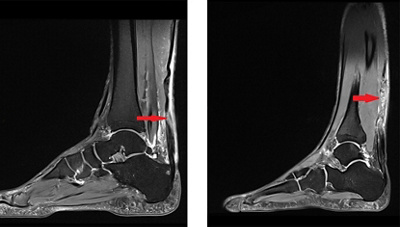

Beim chronischen Riss zwickt es immer mal wieder, der Patient kann aber gut auftreten und die meisten Bewegungen ausführen. Die Schmerzen schleichen sich immer mehr ein, während die Sehne stetig ein Stückchen weiter einreisst. Um einen chronischen Riss eindeutig zu diagnostizieren braucht es eine MRI-Aufnahme. Diese zeigt, ob es sich um einen ein chronischen Riss oder eine andere Erkrankung der Sehne handelt.

2-mri-achillesehnenriss

Zwei MRI-Aufnahmen von gerissenen Achillessehnen